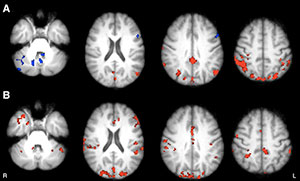

Figure 3. Axial functional connectivity (FC) maps show changes in thalamic FC after 8 weeks in both groups of patients with MS. Areas of increased FC are represented in red, areas of reduced FC in blue. A, Intervention group shows increased FC in occipital, medial, and lateral parietal and posterior cingulate cortices, bilaterally; decreased FC in vermis and left dorsal-lateral prefrontal cortex. B, Wait-list group shows increased FC in frontal, occipital, and medial parietal cortices, bilaterally; cerebellum; and right temporal lobe.

Figure 4. Axial statistical maps show differences in thalamic FC at follow-up in intervention group compared with that in wait-list group. Purple areas represent higher FC increase in intervention group (posterior cingulate gyrus, precuneus, and lateral parietal cortex, bilaterally). Green areas represent lower FC increase in intervention group (vermis, cerebellar hemispheres and left dorsal-lateral prefrontal cortex).